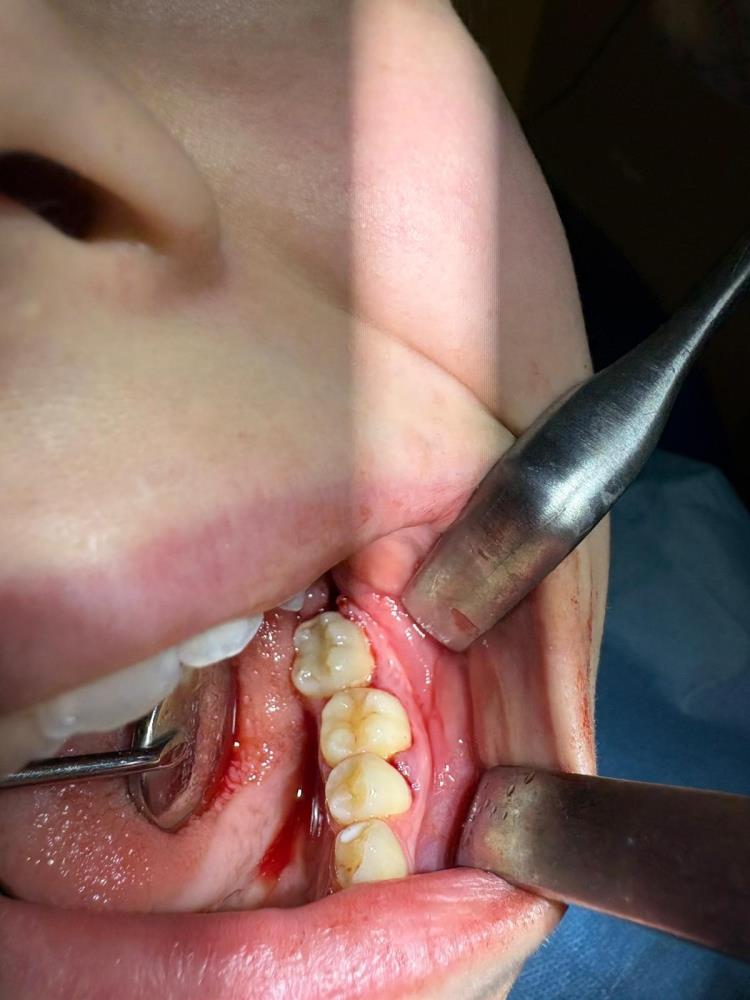

İleri düzey çürük nedeniyle daimi azı dişi çekilen hastaya, yaşı gereği çene gelişimi devam ettiği için klasik implant tedavisi uygun görülmedi. Bunun yerine, hastanın ağzında gömülü halde bulunan yirmi yaş dişi, uzman ekip tarafından cerrahi operasyonla çıkarılarak çekilen dişin yerine nakledildi.

Operasyon sırasında, dişin sağlıklı bir şekilde tutunmasını sağlamak için hastanın kendi kanından elde edilen PRF (Platelet Rich Fibrin) materyali, nakil öncesi hazırlanan diş yuvasına yerleştirildi. Bu uygulama, doku iyileşmesini hızlandıran ve hücre yenilenmesini destekleyen doğal bir yöntem olarak öne çıkıyor. Bu tedavi yöntemi, hastanın kendi dişi kullanıldığı için doğal görünüm, uyum ve fonksiyon açısından büyük avantaj sağlıyor. Aynı zamanda, vücut tarafından kabul edilme oranı yüksek olduğundan, uzun vadeli başarı şansı da oldukça yüksek.

Operasyon, Karabük Üniversitesi Diş Hekimliği Fakültesi Endodonti Anabilim Dalı Öğretim Üyesi Doç. Dr. Olcay Özdemir ve Ağız, Diş ve Çene Cerrahisi Anabilim Dalı Öğretim Üyesi Dr. Öğr. Üyesi Muhammed Abdullah Çege tarafından başarıyla gerçekleştirildi.